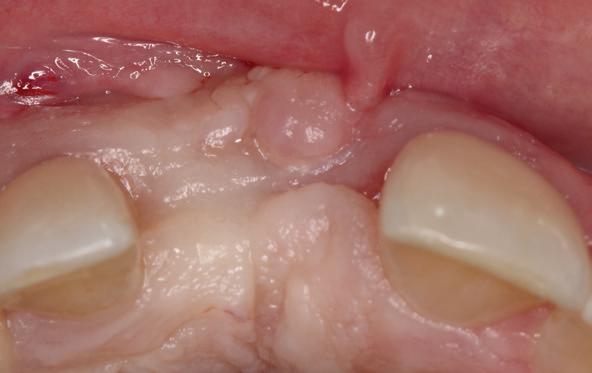

Deze casus beschrijft een uitgebreide immediate implantaatbehandeling bij een patiënt die door meerdere collega’s werd geweigerd. Niet omdat de mogelijkheden ontbraken, maar omdat de complexiteit vroeg om een perfect afgestemde samenwerking. Het verhaal laat zien hoe de assistent in zo’n traject veel meer is dan een uitvoerende kracht of “mal”, maar een dynamische surgical guide die het proces mede stuurt, bewaakt en mogelijk maakt.De patiënt: wanneer alles samenkomt

Ze kwam binnen op een dinsdagochtend, iets voor achten. Een vrouw van begin zeventig, met een zachte stem en ogen die meer vertelden dan haar woorden. Ze vertelde dat ze een eigen B&B had en dat ze zich nauwelijks kon voorstellen gasten te ontvangen zonder tanden. Op dit moment kon ze echter nauwelijks lachen. “Het doet pijn… en het ruikt soms ook niet goed,” zei ze bijna verontschuldigend. Haar oude bovenbrug, die ze al meer dan twintig jaar droeg, was langzaam maar zeker ingestort. Er was sprake van cariës onder meerdere pijlers, pusafvloed,

chronische ontsteking en een brug die mobiel was en elke beet pijnlijk maakte. Ze had inmiddels meerdere tandartsen bezocht. Drie hadden haar geweigerd. Te complex. Te veel wensen. Te onvoorspelbaar.

De kern van haar vraag was eenvoudig en tegelijkertijd uitdagend: Is het mogelijk om mijn huidige brug te dupliceren en een nieuwe brug te vervaardigen met minder complicaties?